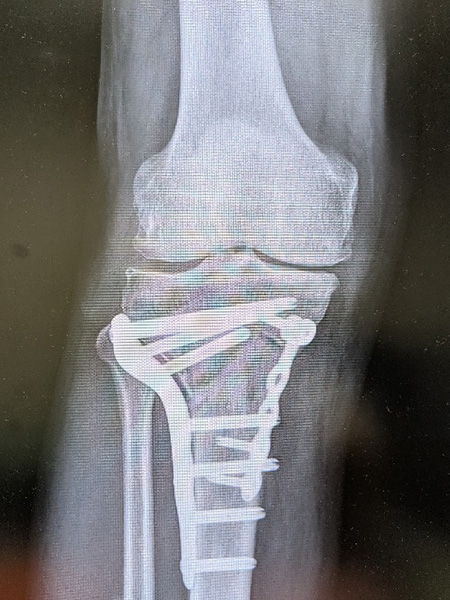

脛骨近位骨切り術

骨切り術は、膝の骨の角度を調整し、関節の負担を分散し痛みの軽減を図る手術です。通常関節鏡視下での半月板手術と併用されることが多く、自身の関節を温存できるため、スポーツや仕事で膝をよく使う方やどうしても人工関節に抵抗がある活動性の高い方に適しています。基本的に術後1年程度で抜釘します。

内側開大脛骨近位骨切り術軽度のO脚変形に対し行われます。

逆V脛骨近位骨切り術高度のO脚変形に対し行われます。